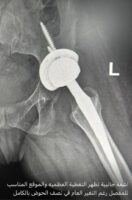

وعن صعوبة الحالة شرح العتيبي أن صعوبة الحالة تكمن في أنه عندما كان عمرها خمس سنوات تزامن لديها كسر الساق الأيمن مع كسر أكبر لمفصل الورك الايسر، حيث أنه لم ينتبه في حينه للكسر في الورك وذلك لأن الكسر الواضح في الساق صرف الانتباه عن الحالة، حيث تم وضع الساق اليمنى في الجبس، ووضع جبيرة للمريضة وهي طفلة وبقيت ملازمة الفراش حتى تم جبر الساق وبقيت على ذلك ٣ أشهر وبعدها تلاشت الآم الورك الأيسر الذي حصل له تغير شامل واختفاء لأهم مظاهره الطبيعية ليفقد رقبة الورك وحُق الورك وتغير شكل رأس عظمة الفخذ وحدث قصور في الطرف السفلي الايسر ما يقرب من ٤ ونصف سم وضمور عضلي شديد وكبرت الطفلة ،وهي تعاني حتى عمر ٢٥ سنة دون معرفة الأسباب الحقيقية خلف المعاناة .

مضيفاً : وصلت المريضة للمستشفى وتم إجراء كافة التحاليل والفحوصات والإشاعات المطلوبة و التي أكدت إمكانية إجراء عملية تغيير مفصل كامل للورك بأمان رغم صعوبة التغيرات العظمية للورك وضمور العضلات وقصر الرجل وتمت العملية بنجاح ولله الحمد لتضاف للجراحات النوعية في جراحة استبدال مفصل الورك التي تتم في المستشفى ،وتؤكد على تطور الخبرات الطبية بالمستشفى بأحدث التقنيات الطبية الحديثة المتطورة عالمياً.